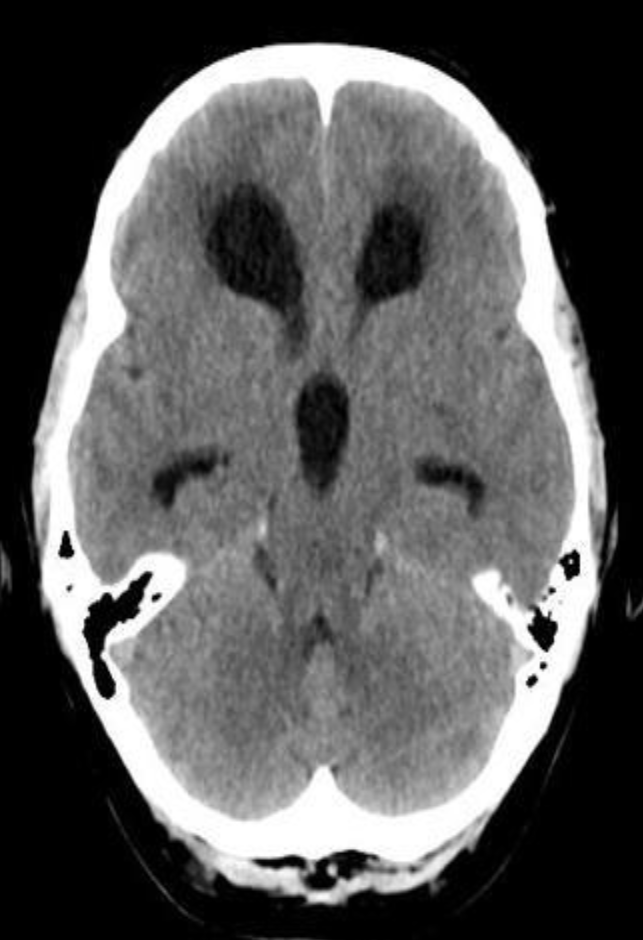

A. Imaging study. *CT head *(without contrast; axial plane)

B. What is the most likely diagnosis? Subarachnoid hemorrhage

- Multiple areas of high attenuation in the basal cisterns, Sylvian fissures, and sulci are

- characteristic of extensive subarachnoid hemorrhage.